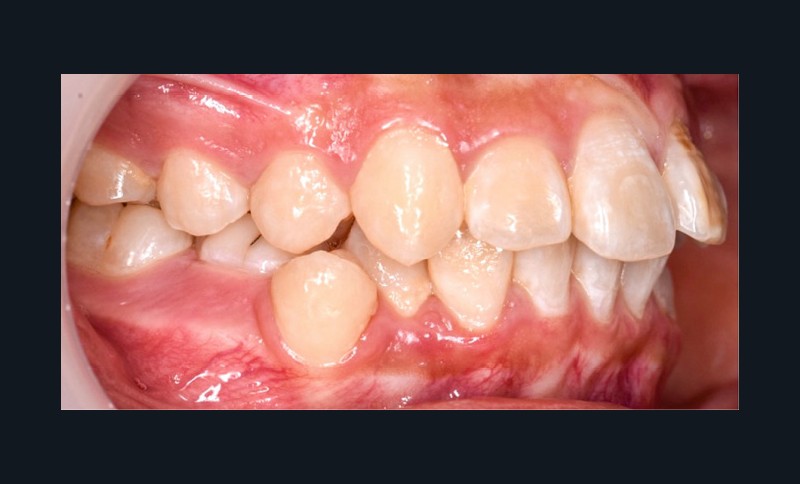

Une patiente âgée de 12 ans se présente en consultation, motivée par la position de son incisive centrale maxillaire, décrite comme « en avant », marquée par une dyschromie et une mobilité de grade 2 selon Muhlemann. L’examen clinique montre l’absence de 23 sur l’arcade, une dysharmonie dents-arcade marquée, un surplomb accentué, et une déviation des milieux inter-incisifs, conséquence du comblement spontané de l’espace de 23. L’ensemble s’inscrit dans un contexte de Classe I d’Angle molaire. L’orthopantomogramme révèle l’inclusion de 23, associée à une résorption radiculaire étendue aux deux tiers de 21. La 22 ne présente aucune altération visible.

La patiente, de profil normodivergent, présente une Classe I squelettique sans troubles fonctionnels (fig. 1-8).